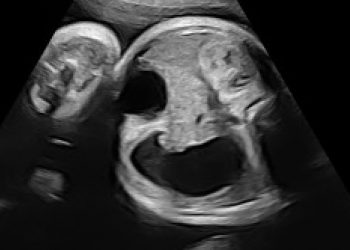

Per il mese di Dicembre SIEOG Giovani presenta il Webinar sullo screening delle cardiopatie congenite nel primo trimestre. La registrazione...